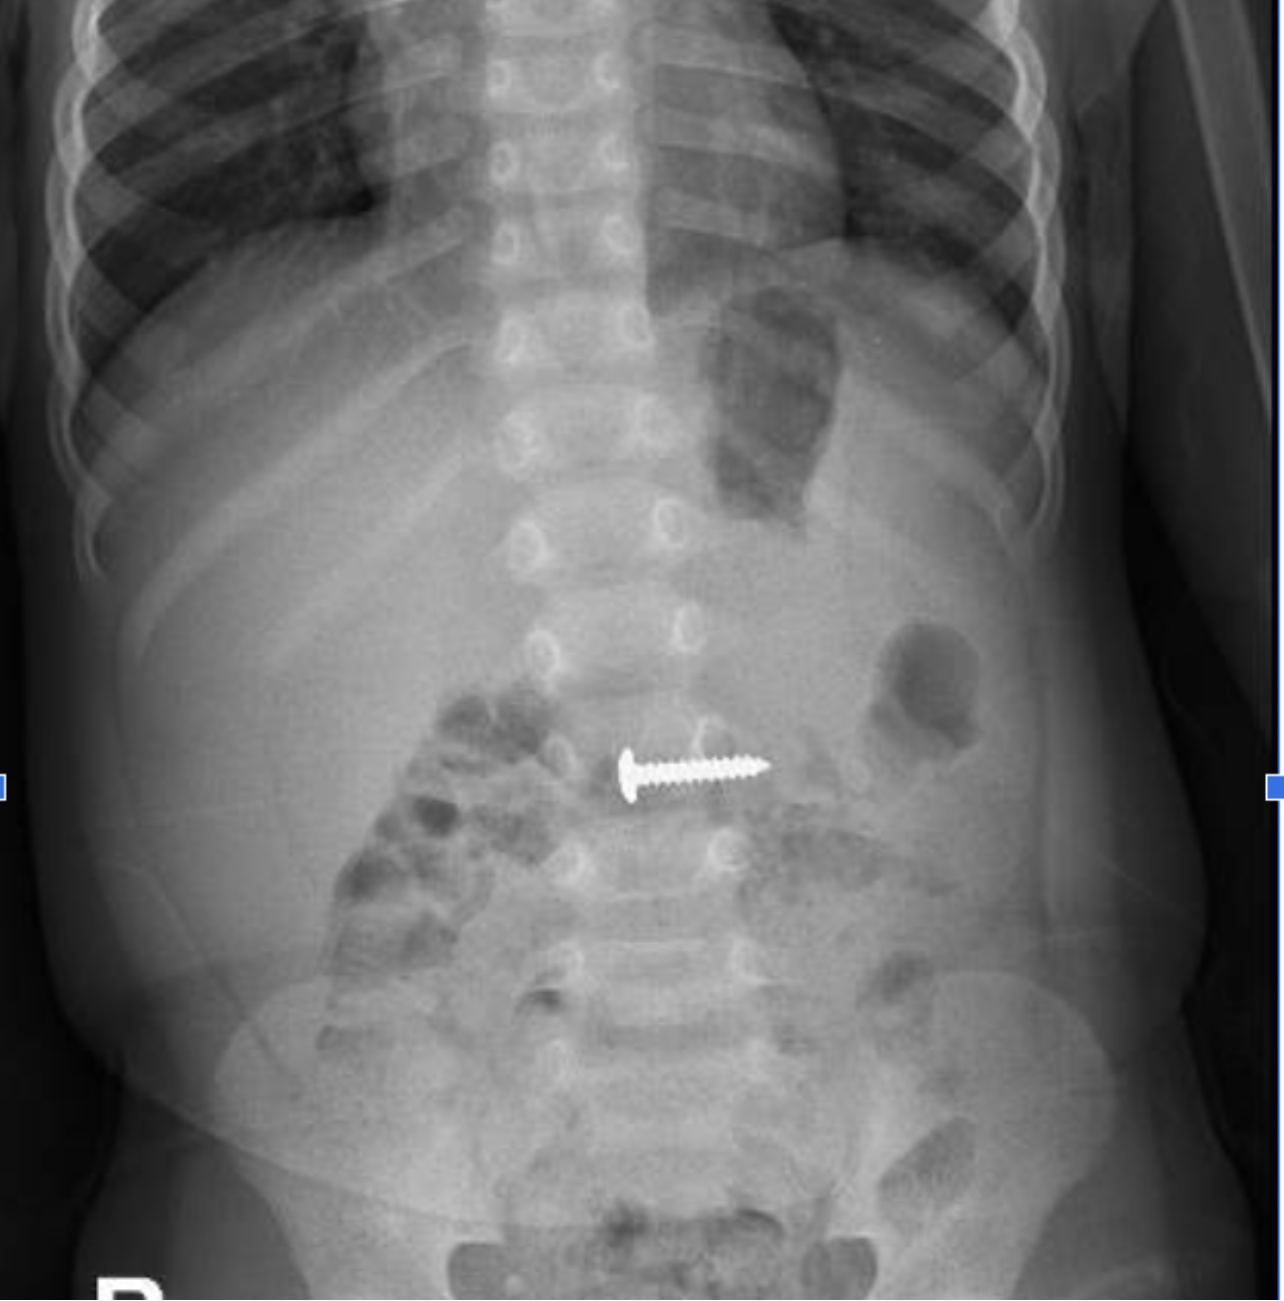

| Hình ảnh chụp X-quang của bệnh nhi H. Ảnh: BVĐKQT |

Bệnh nhi H. được các bác sĩ Khoa Ngoại Tổng hợp, Bệnh viện Đa khoa tỉnh Quảng Trị tiến hành khám và chỉ định chụp X-quang bụng không chuẩn bị thẳng, phát hiện dị vật nằm trong đường tiêu hóa, có kích thước 24,15mm.